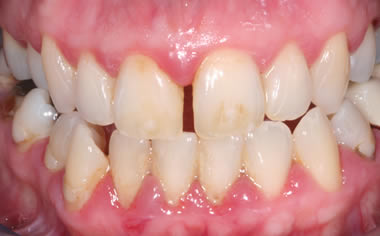

Gum disease

Case One (2 images)

Treatment of severe gum disease.

Case Two (2 images)

Treatment of moderate gum disease.